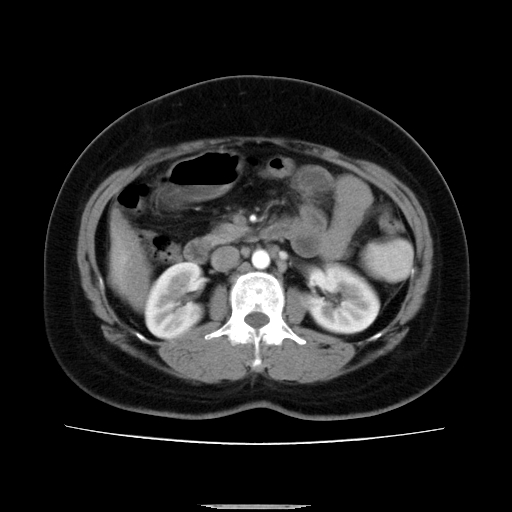

标题: CT14225:女性46岁。当地B超示肝内占位,来我院作CT检查。请 [打印本页]

标题: CT14225:女性46岁。当地B超示肝内占位,来我院作CT检查。请

右叶肝癌灶;慢性胆囊炎,不除外占位;;副脾可能性

肝内结节强化特点符合原发性肝癌表现,脾脏改变考虑为增大及先天发育所致。

支持肝癌、胆囊炎诊断。

符合肝癌表现,脾脏大(肝硬化?)

非常典型,肝ca,脾脏先天性发育异常,脾大

肝内结节强化特点符合原发性肝癌表现。脾大。

快进快出,符合肝癌表现。脾脏改变考虑为增大及先天发育所致。